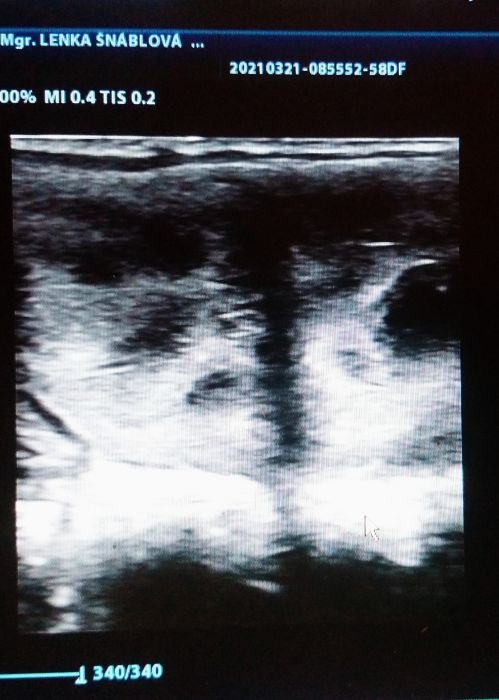

Říjová děloha klisny

V připouštěcím období je většina inseminačních techniků na roztrhání…:) Pokud majitel zná dobře svoji klisnu, ví, jak dlouhé má říje a je si vědom toho, že klisna ovuluje na konci říje, nemusí inseminačního technika volat často, stačí v druhé půlce říje. Bez USG vyšetření ovšem ovulaci detekujeme jen velmi těžko. Spousta chovatelů se domnívá, že stačí připustit – inseminovat klisnu jednou v říji, ovšem dělají chybu, že připouští již na začátku říje a nezkontrolují si, zda klisna zovulovala. Negativní výsledek – tedy nezabřeznutí pak často padá na hlavu majitele hřebce. Není ale tomu tak, důvodem je, jak jsem již zmínila, že klisna nezovulovala, tedy vajíčko (které je do vejcovodu vypuzeno z folikulu po prasknutí), nemělo šanci být oplodněno. Pokud má klisna tichou říji, tzn. že nejsou vidět vnější příznaky říje (blýskání aj.), je potřeba volat inseminačního technika, aby zjistil, v jakém stadiu cyklu se klisna nachází, zda není třeba těsně po říji, zda není v anestru (zimním necyklickém období), nebo zda klisna nastupuje do říje. Tohle všechno pozná inseminační technik na základě stavu dělohy (zda je edematická), velikosti folikulů na vaječnících (většinou klisně roste dominantní folikul na jednom z vaječníků), zda je či není přítomno žluté tělísko. Podle doby cyklu odhadne, kdy asi začne klisna říjet či kdy přibližně nastane doba ovulace.